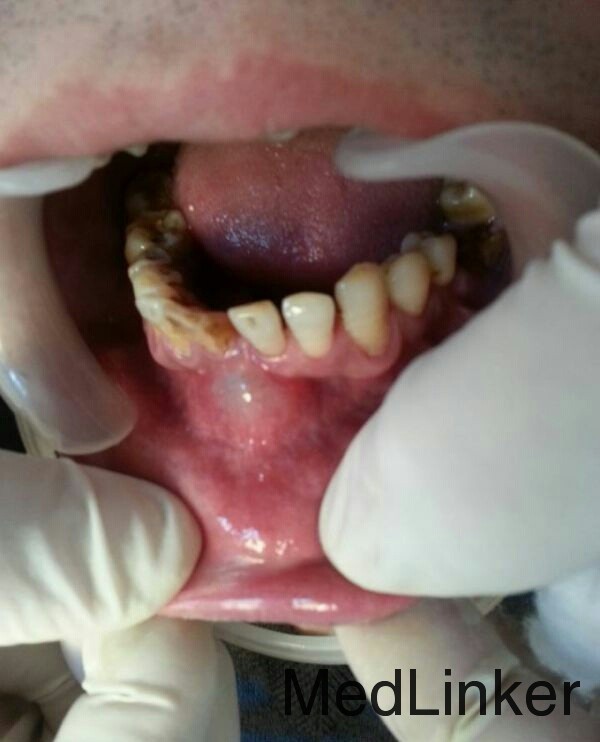

下前牙肿物

患者男,36岁,下前牙龈肿物数日,压痛红肿。

下前牙区多生牙

下颌前牙区肿物